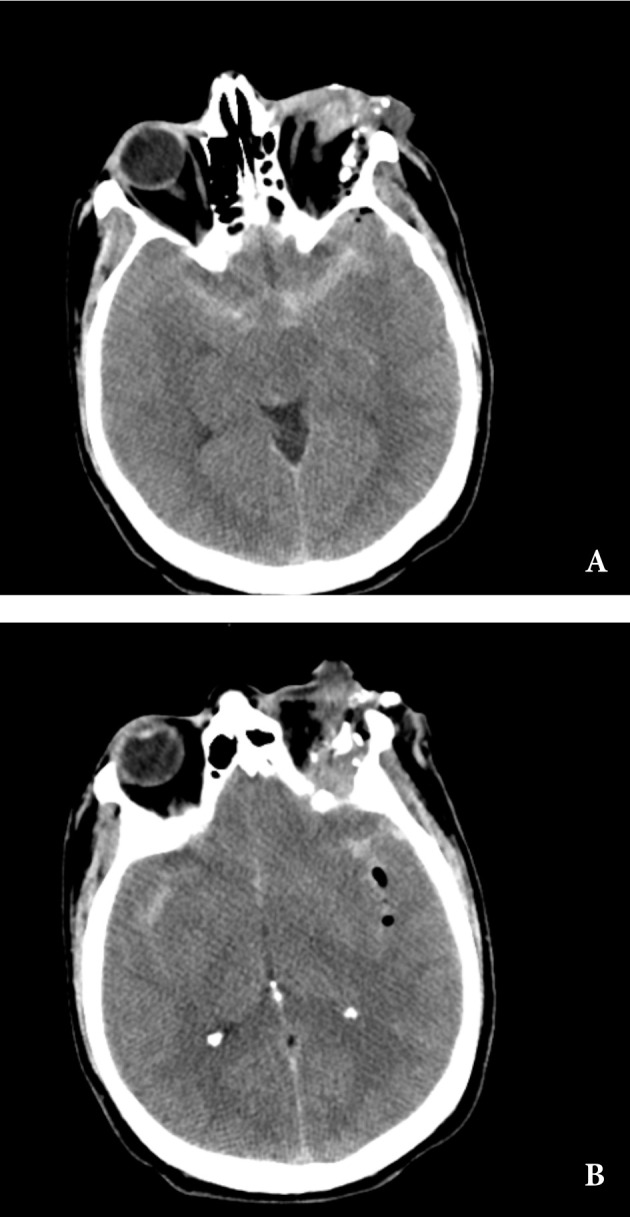

患者男性,39岁,既往健康,无特殊病史。在使用圆锯进行机械作业期间遭受非飞弹性经眶穿入大脑及左眼穿孔,后被转移到急诊室(图1)。他到达时处于昏迷状态,对机械刺激无反应,但血液动力学稳定,能自主呼吸。左眶顶是异物进入大脑的路径。

紧急头部CT显示在左眼眶外侧和左外直肌(可能是入口伤口)中有多个骨碎片和金属异物(图2 a),以及左眼眶的上方和后方有被压碎的眼球(图2 b)。颅内可见造成脑实质创伤性损伤的投射物路径,充满含气小气泡并被蛛网膜下腔出血包围(图2 b)。它还显示了贯穿整个脑实质的充满血液的穿透伤口撞击通道,从左侧颞底区域向上蔓延到左侧顶叶,其中充满了残留的异物/骨碎片和少量空气(图3 a)。一个尖锐的金属物体卡在左顶叶皮质下,垂直于顶骨(图3 b、c和d)。计算机断层血管造影(CTA)显示脑血管没有明显的血管损伤,但由于金属伪影,成像受到限制。